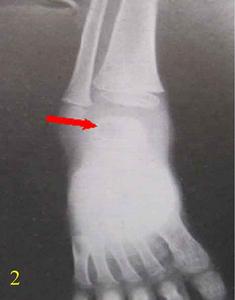

局限性骨膿腫1、X線檢查:表現為長骨幹骺端有橢圓形密度減低區,邊緣有清晰的骨質硬化,病變與鄰近正常骨髓腔境界清楚。需與骨囊腫鑑別。骨囊腫周圍只有薄層成帶狀硬化骨。

X線片表現為骨端有局限性密度減低區,其周圍骨質有炎性反應性增高陰影,且與周圍骨質分界不清一般多無骨膜反應及死骨。此種狀態應與骨囊腫鑑別後者主要顯示為囊腔周圍只有薄層帶狀硬化骨。